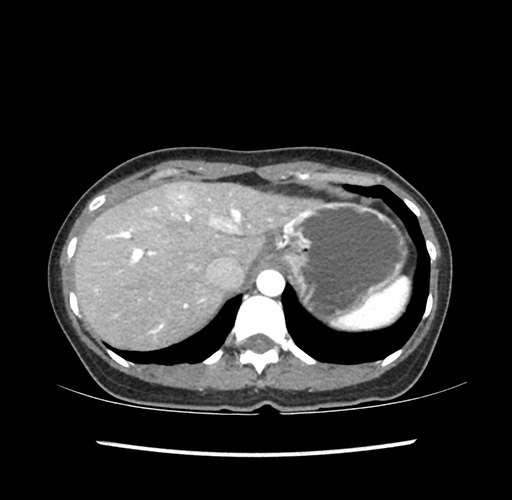

Imaging Analysis

Look through the patient's CT scan to identify any areas of concern for the necessary procedure.

Based on your CT findings, which issue(s) would give reason for "planned slowing down moment(s)" in this case?

Considering a standard left lateral sectionectomy procedure, what step(s) of the operation would you do differently in this case ?